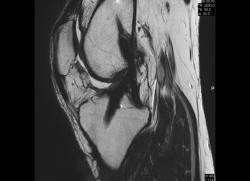

Resonancia magnética

Se basa en la propiedad que poseen los núcleos de hidrógeno de absorber energía electromagnética cuando están sometidos a un campo magnético intenso. La RM representa un mapa de la densidad de protones, o sea, de la distribución de agua por el organismo(12).

Se consiguen unas imágenes de alta resolución para la valoración de meniscos, ligamentos y tendones. Además, es especialmente útil en las rodillas operadas, lesiones tumorales, evaluación del cartílago y la visualización de los nervios(13).

1. Estudio de las estructuras intraarticulares

Es la prueba no invasiva de elección para valorar las lesiones internas de la rodilla(2). Aunque el estudio por RM es a menudo considerado como la prueba diagnóstica de elección para la detección de alteraciones meniscales, se asocia en ocasiones con errores diagnósticos(16).

1.1. Meniscos

Se identifican como estructuras hipointensas en todas las secuencias, con asta anterior y posterior de morfología triangular.

La RM es la técnica de elección en el diagnóstico de la patología meniscal(17)(Figuras 30, 31, 32, 33, 34 y 35).